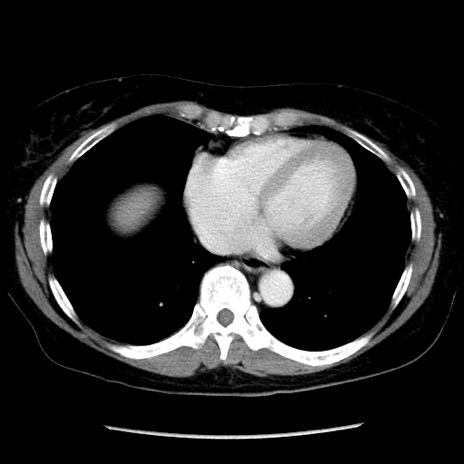

症例6(横断像)

【症例】50歳代女性

【主訴】下腹部痛

【現病歴】本日朝より下痢2回あり。 昼食を食べた後、嘔吐3回、下腹部痛認め、症状軽快せず、当院救急搬送。

最終食事:本日昼(生ものなし)。 昨日の夜、刺身を食ぺたとのこと。周囲に同様の症状の者なし。普段、排便は毎日あるとのこと。

【既往歴】卵巣癌術後(8年前に当院で卵巣摘出)

【身体所見】 意識清明、腹部:平坦、腸蠕動音→、やや硬、下腹部自発痛・圧痛あり、反跳痛あり、筋性防御なし。

【データ】WBC 16000、CRP 0.01